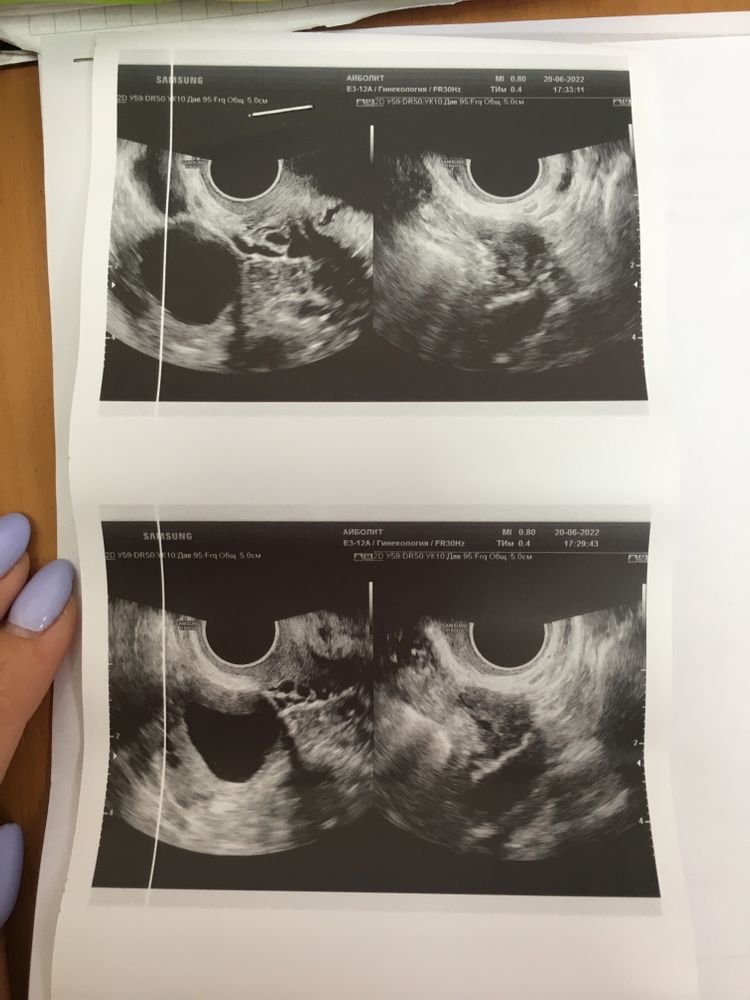

В итоге сходила вчера на УЗИ и толком ничего не поняла, врач не пояснила. Сказала что не может понять, как будто должна скоро начаться овуляция но при этом эндометрий маленький. Также поставила под вопросом МФЯ. Сказал сделать ещё раза фолликулометрию и иди к гинекологу с результатами.

Девочки посмотрите пожалуйста мои анализы и результаты УЗИ. Может вы что-то поймёте и мне объясните. Не могу ни как себя успокоить, переживаю. Даже работать не получается(